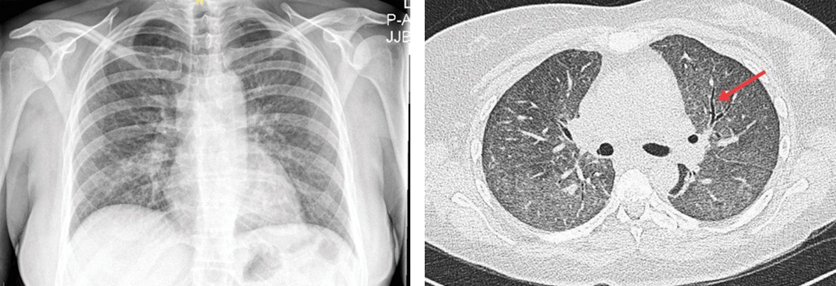

肺部感染胸片图,正常胸片和肺炎胸片图

一文搞定:不同类型肺部感染的ct征象与鉴别诊断

图3 40岁女性的胸片显示双肺弥漫性间质性改变 胸部ct示双肺弥漫性磨